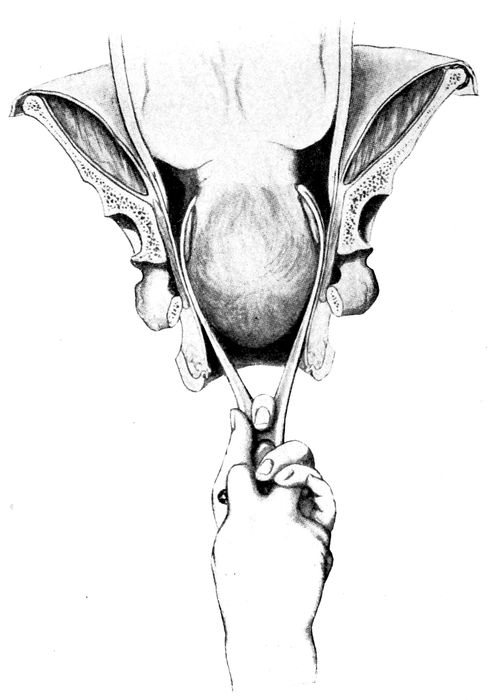

| 81. |

191 |